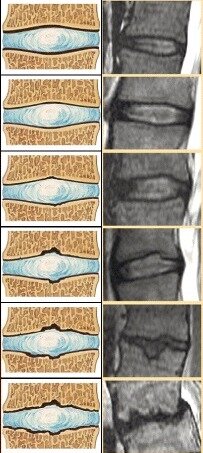

Disc degenerative disease (between vertebrae) from none to severe